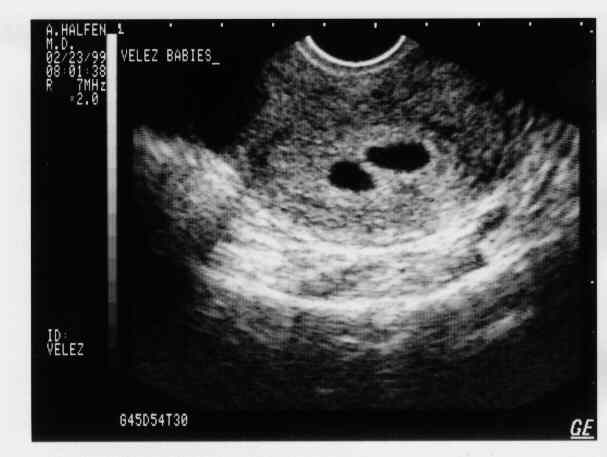

V-Twins

eggs2.JPG - 19.8 K eggs3.JPG - 22.4 K eggs4.JPG - 11.7 K babies-1a.JPG - 21.3 K